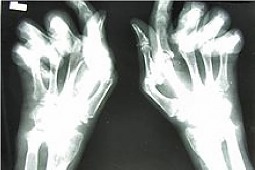

Teorie te wydają się potwierdzać wyniki, opublikowanego na łamach Journal of Bone and Mineral Research, badania obejmującego populację blisko 20 tys. chorych na reumatoidalne zapalenie stawów (RZS), których dane zgromadzone zostały w narodowej bazie danych (National Data Bank for Rheumatic Diseases), na przestrzeni lat 2003 – 2011. Ryzyko zawału mięśnia serca było istotnie mniejsze wśród chorych na RZS stosujących bisfosfoniany, w porównaniu do nie leczonych tymi lekami (0,72), po uwzględnieniu występujących czynników ryzyka sercowo-naczyniowego, aktywności choroby podstawewej oraz sprawności. W wyselekcjonowanej grupie pacjentów, którzy kiedykolwiek stosowali bisfosfoniany, cęstość zawału była mniejsza u chorych aktualnie przyjmujących bisfosfonian (0,56), w porównaniu do chorych nie leczonych. Wykazano ponadto, że najsilniejszy efekt protekcyjny miało stosowanie kombinacji trzech leków: bisfosfonian, witamina D, wapń.